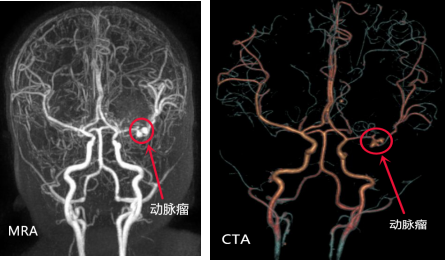

王广宇主任团队随即为萌萌安排了脑室外引流术,经过积极救治,萌萌的病情暂时稳定了下来,意识也逐渐清醒。但患儿脑内出血的原因尚不明确,王广宇主任分析,脑内出血最常见于脑动静脉畸形出血,但也不能排除动脉瘤出血或其他原因出血,必须进一步完善相关检查,明确出血根本原因,进一步从根本上治疗。王广宇主任团队随即为萌萌安排了颅脑CTA、MRA及脑血管造影等检查,结果不出所料,萌萌最终诊断为大脑中动脉动脉瘤。这一结果又是大家最不想看到的。

颅内动脉瘤被称为是颅内的不定时“炸弹”。它是指颅内动脉血管壁异常突起形成的囊状包块,最常见的原因有长年高血压、外伤、先天发育异常等。这个“炸弹”不知道什么时候破裂,且存在反复出血可能,出血严重者短时间内即可死亡。

王广宇表示,像萌萌这么小的幼儿大脑中动脉动脉瘤,还是比较少见的,不同于成人动脉瘤,无法行介入栓塞,只能靠开颅手术夹闭,但萌萌的动脉瘤位于大脑中动脉主干,术前动脉瘤远端血管尚未完全闭塞,但开颅手术夹闭过程中可能出现远端血管闭塞缺血导致大面积脑梗塞,甚至弥漫性脑水肿,生命危险等,且手术过程中一旦发生动脉瘤破裂,可能会引发大出血甚至死亡,抢救都来不及。